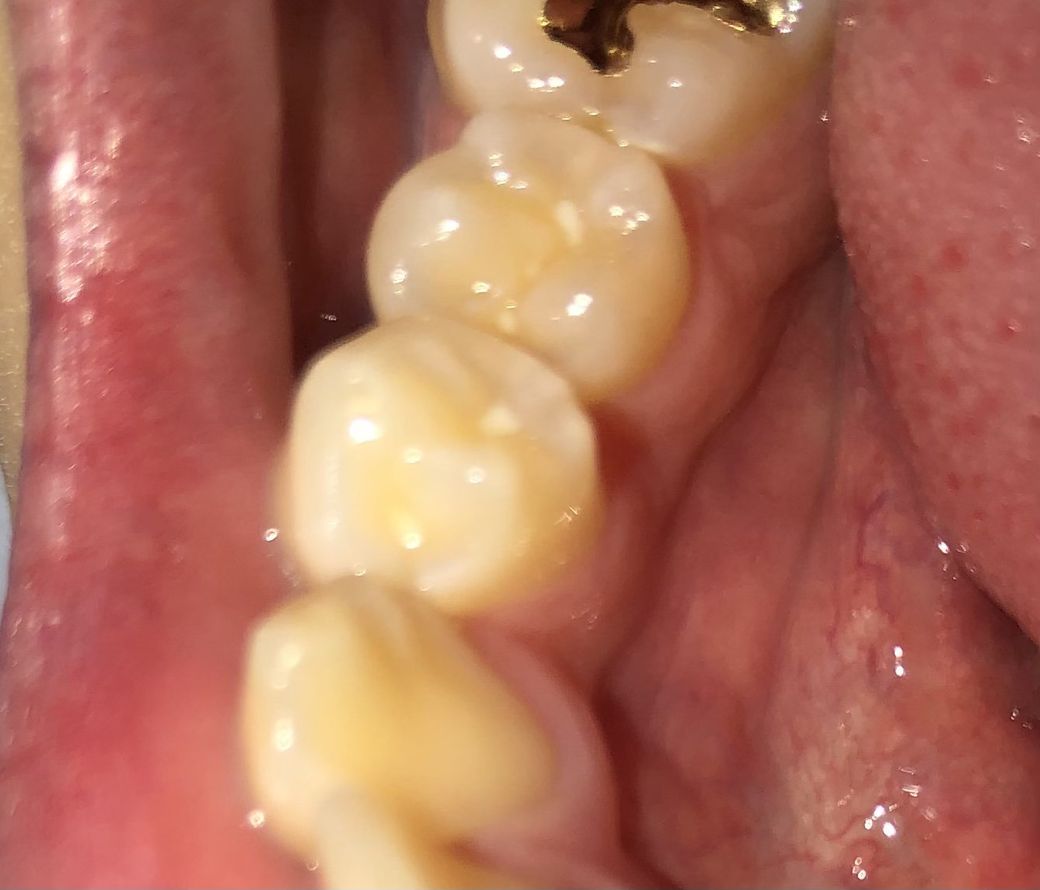

Ps. 사진에 보이는 것처럼 이 부분에 흰색이 있는데 썩은건가요?? 아니면 뭐예요?!??

사진에 보이는 하얀색은 흐려서 정확하지는 않지만 치과충전재 또는 음식물이 홈에 껴있는것으로 보입니다.

사진이 흐려서 정확하진 않지만 사진상에 보이는 흰색은 아마 충치치료후 충전한 치과 재료 같습니다.

치아에 흰 색 부분은 치태이거나 접착제 잔사거나 어릴적 실란트를 한 부분일 것 같네요.

사진의 상이 명확하지 않지만, 사진의 하얀 부분은 음식 잔사가 남아 있는 것이거나, 예전에 예방치료인 실런트를 한 것일 가능성이 있어 보입니다.

사진에 보이는 흰색은, 음식물이 아니라면, 실런트인것으로 보이나,

정확한것은 직접봐야 알 수 있어서 확실히 말씀드리긴 어렵습니다. 감사합니다.